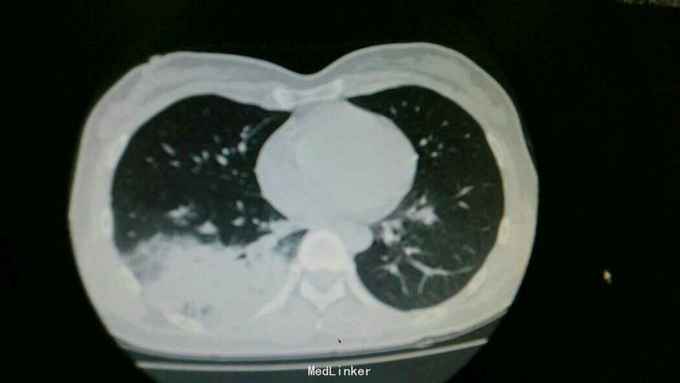

查体:右下肺可闻及湿性啰音。余无特殊。 辅查:右肺下叶大叶性肺炎。

诊断:大叶性肺炎。 治疗:入院予以抗感染,止咳化痰等治疗。